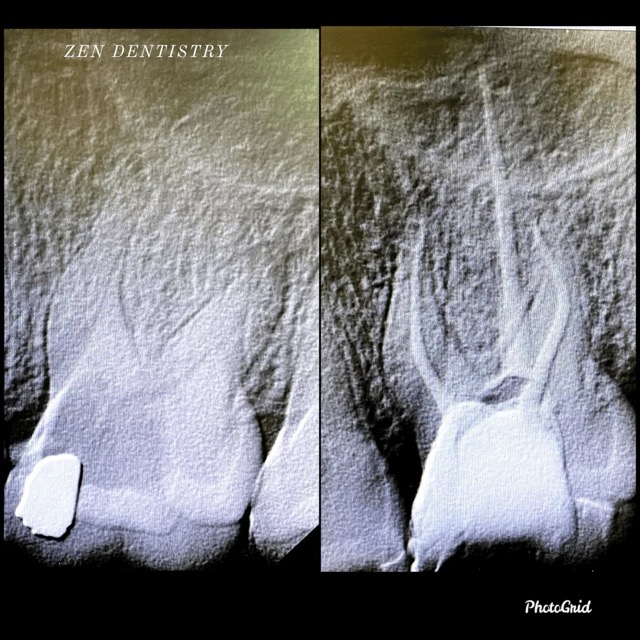

Patient presented to the office with a concern that the tooth has been causing severe constant pain that would become worse at night time and biting. A detailed clinical exams including endodontic screening and x rays let to the diagnosis of pulp necrosis (dead nerve)due to gross dental caries that reached the nerve of the tooth with symptomatic apical periodontitis (inflamed ligaments).

Root Canal treatment was performed that included removing the caries, dead nerve tissue and disinfecting the canals with proper medication to achieve a 3D hermetic seal of the canals to save the tooth.